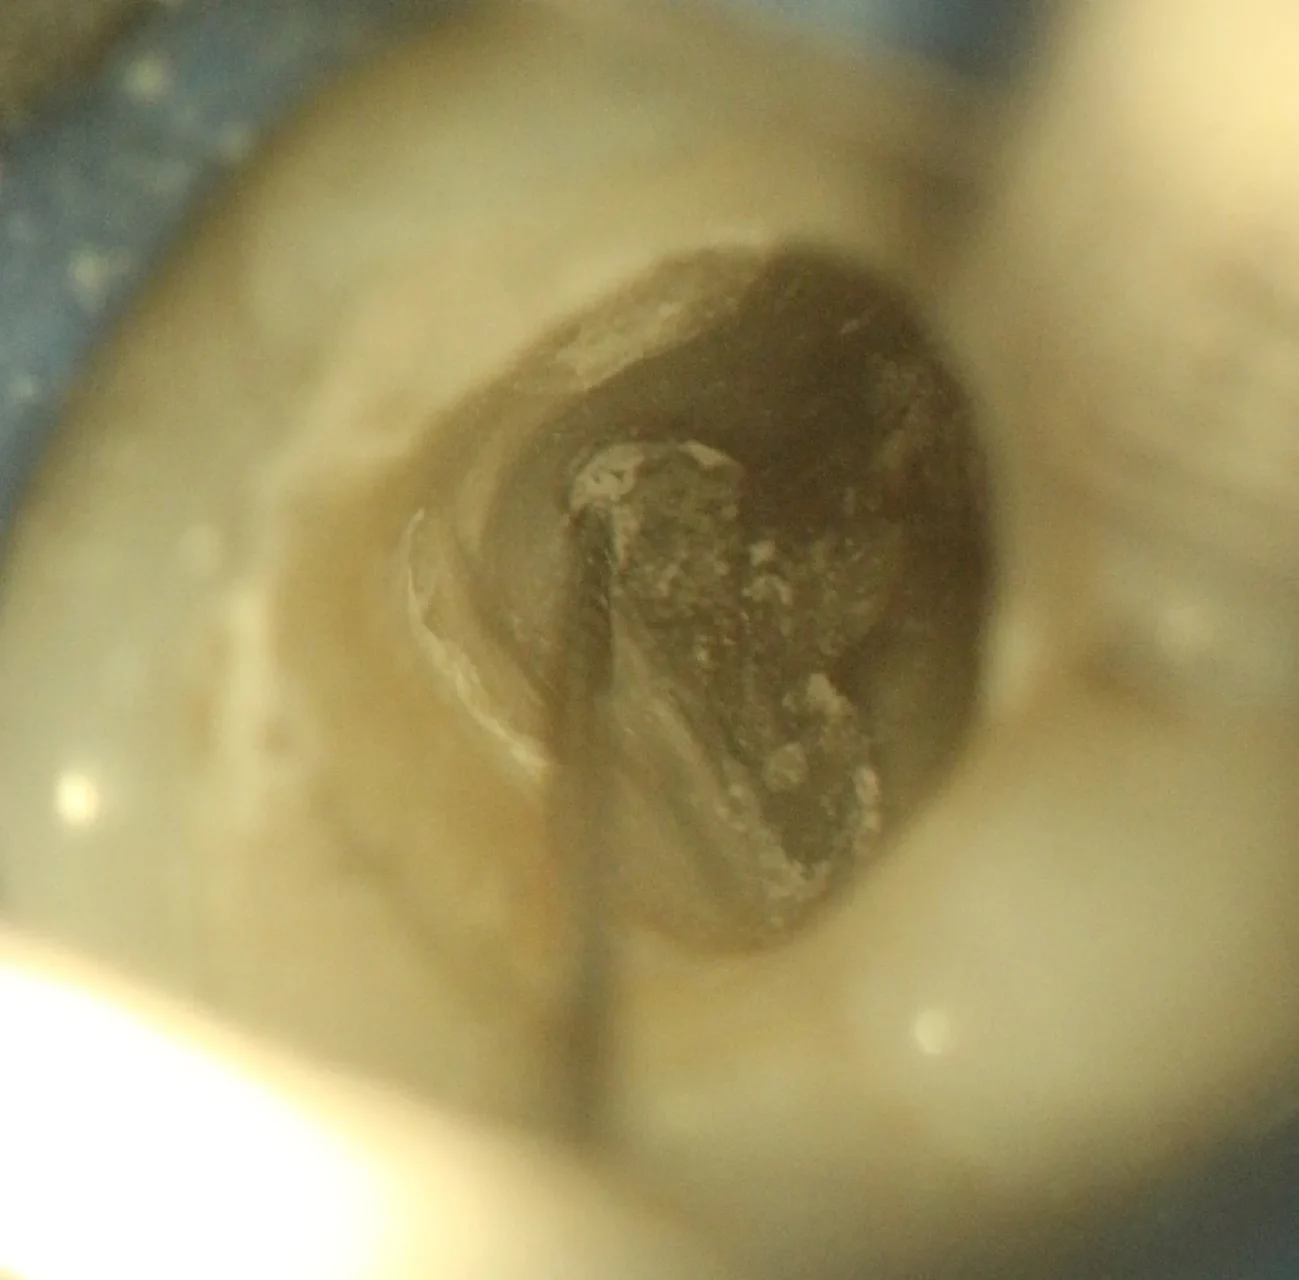

Localização de Canais Calcificados

Microscópio auxiliando na limpeza e localização de canais calcificados

Calcificação Pulpar

Após remoção do cálculo e localização dos canais

Auxílio do microscópio na localização e limpeza